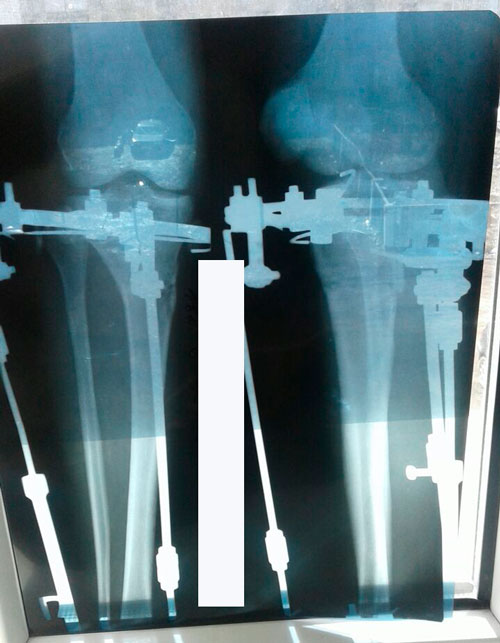

В процессе сращения.

Стараемся равномерно распределять центр тяжести на обе ножки.

В данный момент, щадим левую ногу. А так, всё в норме!

Рентген в 60 дней.

Процесс сращения идёт хорошо, ждём повторный рентген в 85 дней.